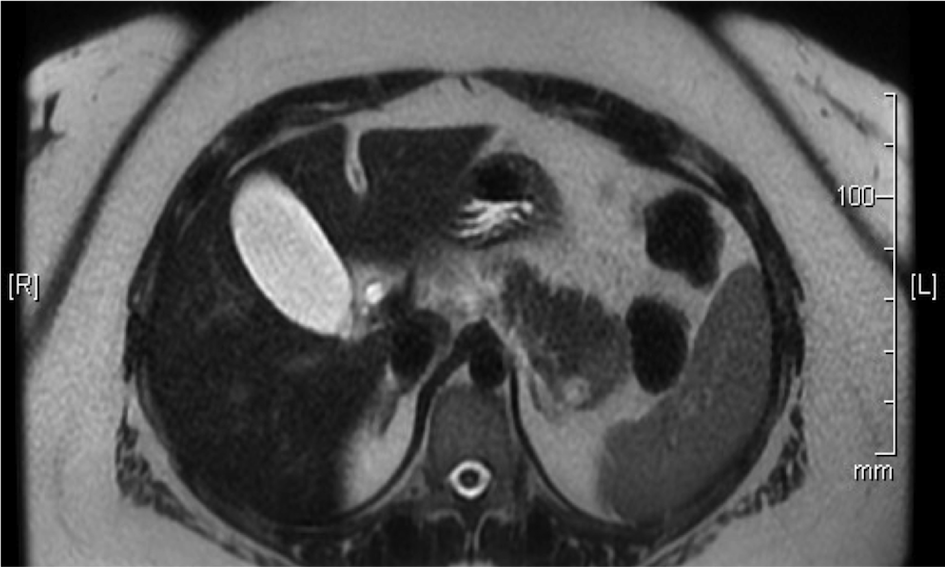

A 32-year-old Hispanic woman presented with recent onset of moderate right upper quadrant abdominal pain. The pain was not associated with any aggravating or relieving factors and gradually resolved during her hospital stay. Past history was significant for obesity and hysterectomy. Physical examination showed normal vital signs and mild upper abdominal discomfort on deep palpation. Comprehensive laboratory work-up was unremarkable. A non-contrast computed tomography (CT) of the abdomen showed a vague lesion in the pancreatic tail. A contrast-enhanced magnetic resonance imaging (MRI), done to better characterize the lesion, showed a 4-cm pancreatic tail mass, and a 1-cm cystic area in that mass (Figure 1). Endoscopic ultrasound (EUS) showed a 4-cm oval, hypo-echoic solid mass in the pancreatic tail, and a 1-cm an-echoic (cystic) area within that mass. Fine needle aspiration of the mass showed well-circumscribed lymphoid aggregates, without monoclonal expansion, mixed with red blood cells. For concerns of malignancy, the patient underwent distal pancreatectomy with splenectomy. The resected specimen showed a well-circumscribed 4-cm red-brown lobulated mass representing ectopic spleen with reactive lymphoid hyperplasia (Figure 2) (Figure 3), and a 0.7-cm multilocular benign squamous cyst within the accessory spleen (Figure 4). Post-operative course was unremarkable and the patient was discharged home in a stable condition.

Figure 1 The T2 diffusion-weighed cross sectional images of the MRI. There is 4cm hypo-intense pancreatic tail lesion, and a 1cm T2 bright cystic structure within that lesion.

Despite their rarity, epidermoid cysts in IPAS should be recognized as a differential diagnosis of pancreatic tail lesions in appropriate clinical setting. Non-invasive imaging modalities (CT or MRI) may aid in diagnosing the epidermoid cyst in the IPAS. On multi-phasic dynamic CT scan, IPAS has the same attenuation as native spleen. Since attenuation of spleen is higher than pancreas, IPAS appears brighter than pancreas on all three phases of CT scan, this is in contrast to other hypervascular lesions of pancreas that may become iso- or hypo-attenuating to the adjoining pancreas on the venous phase. On MRI, epithelial cysts commonly show low signal intensity on T1-weighted images and high signal on T2-weighted images. The ectopic splenic tissue shows a spleen-like signal on diffusion-weighted images. Adequate amount of splenic tissue around the cyst makes the diagnosis of epidermoid cyst in IPAS easy, otherwise diagnosis before surgery remains challenging.6